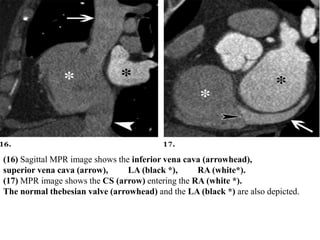

Right Side of the Heart

Depending on the injection protocol used, varying levels of

enhancement of the right side of the heart are achieved. If this side of

the heart is enhanced with contrast material, the RA, RV, and tricuspid

valves can be assessed in detail.

The eustachian valve is located at the RA–inferior vena cava junction

and directs flow toward the foramen ovale.

The thebesian valve prevents reflux from the RA into the CS.

(16) Sagittal MPR image shows the inferior vena cava (arrowhead),

superior vena cava (arrow), LA (black *), RA (white*).

(17) MPR image shows the CS (arrow) entering the RA (white *).

The normal thebesian valve (arrowhead) and the LA (black *) are also depicted.